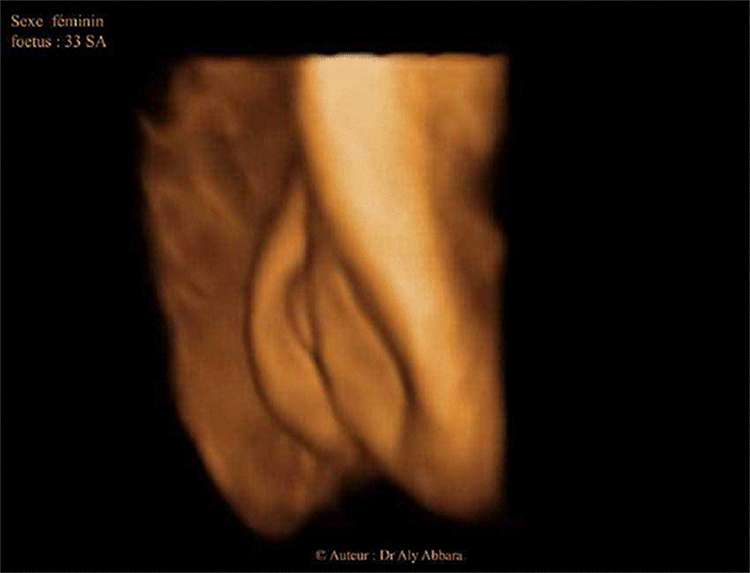

Organes génitaux externes chez un foetus du sexe féminin ; 33 SA

Images animées en 3D montrant l'aspect échographique des éléments anatomiques des organes génitaux externes chez un fœtus du sexe féminin à 33 SA et un fœtus du sexe masculin à 37 SA

Auteur : Dr Aly Abbara